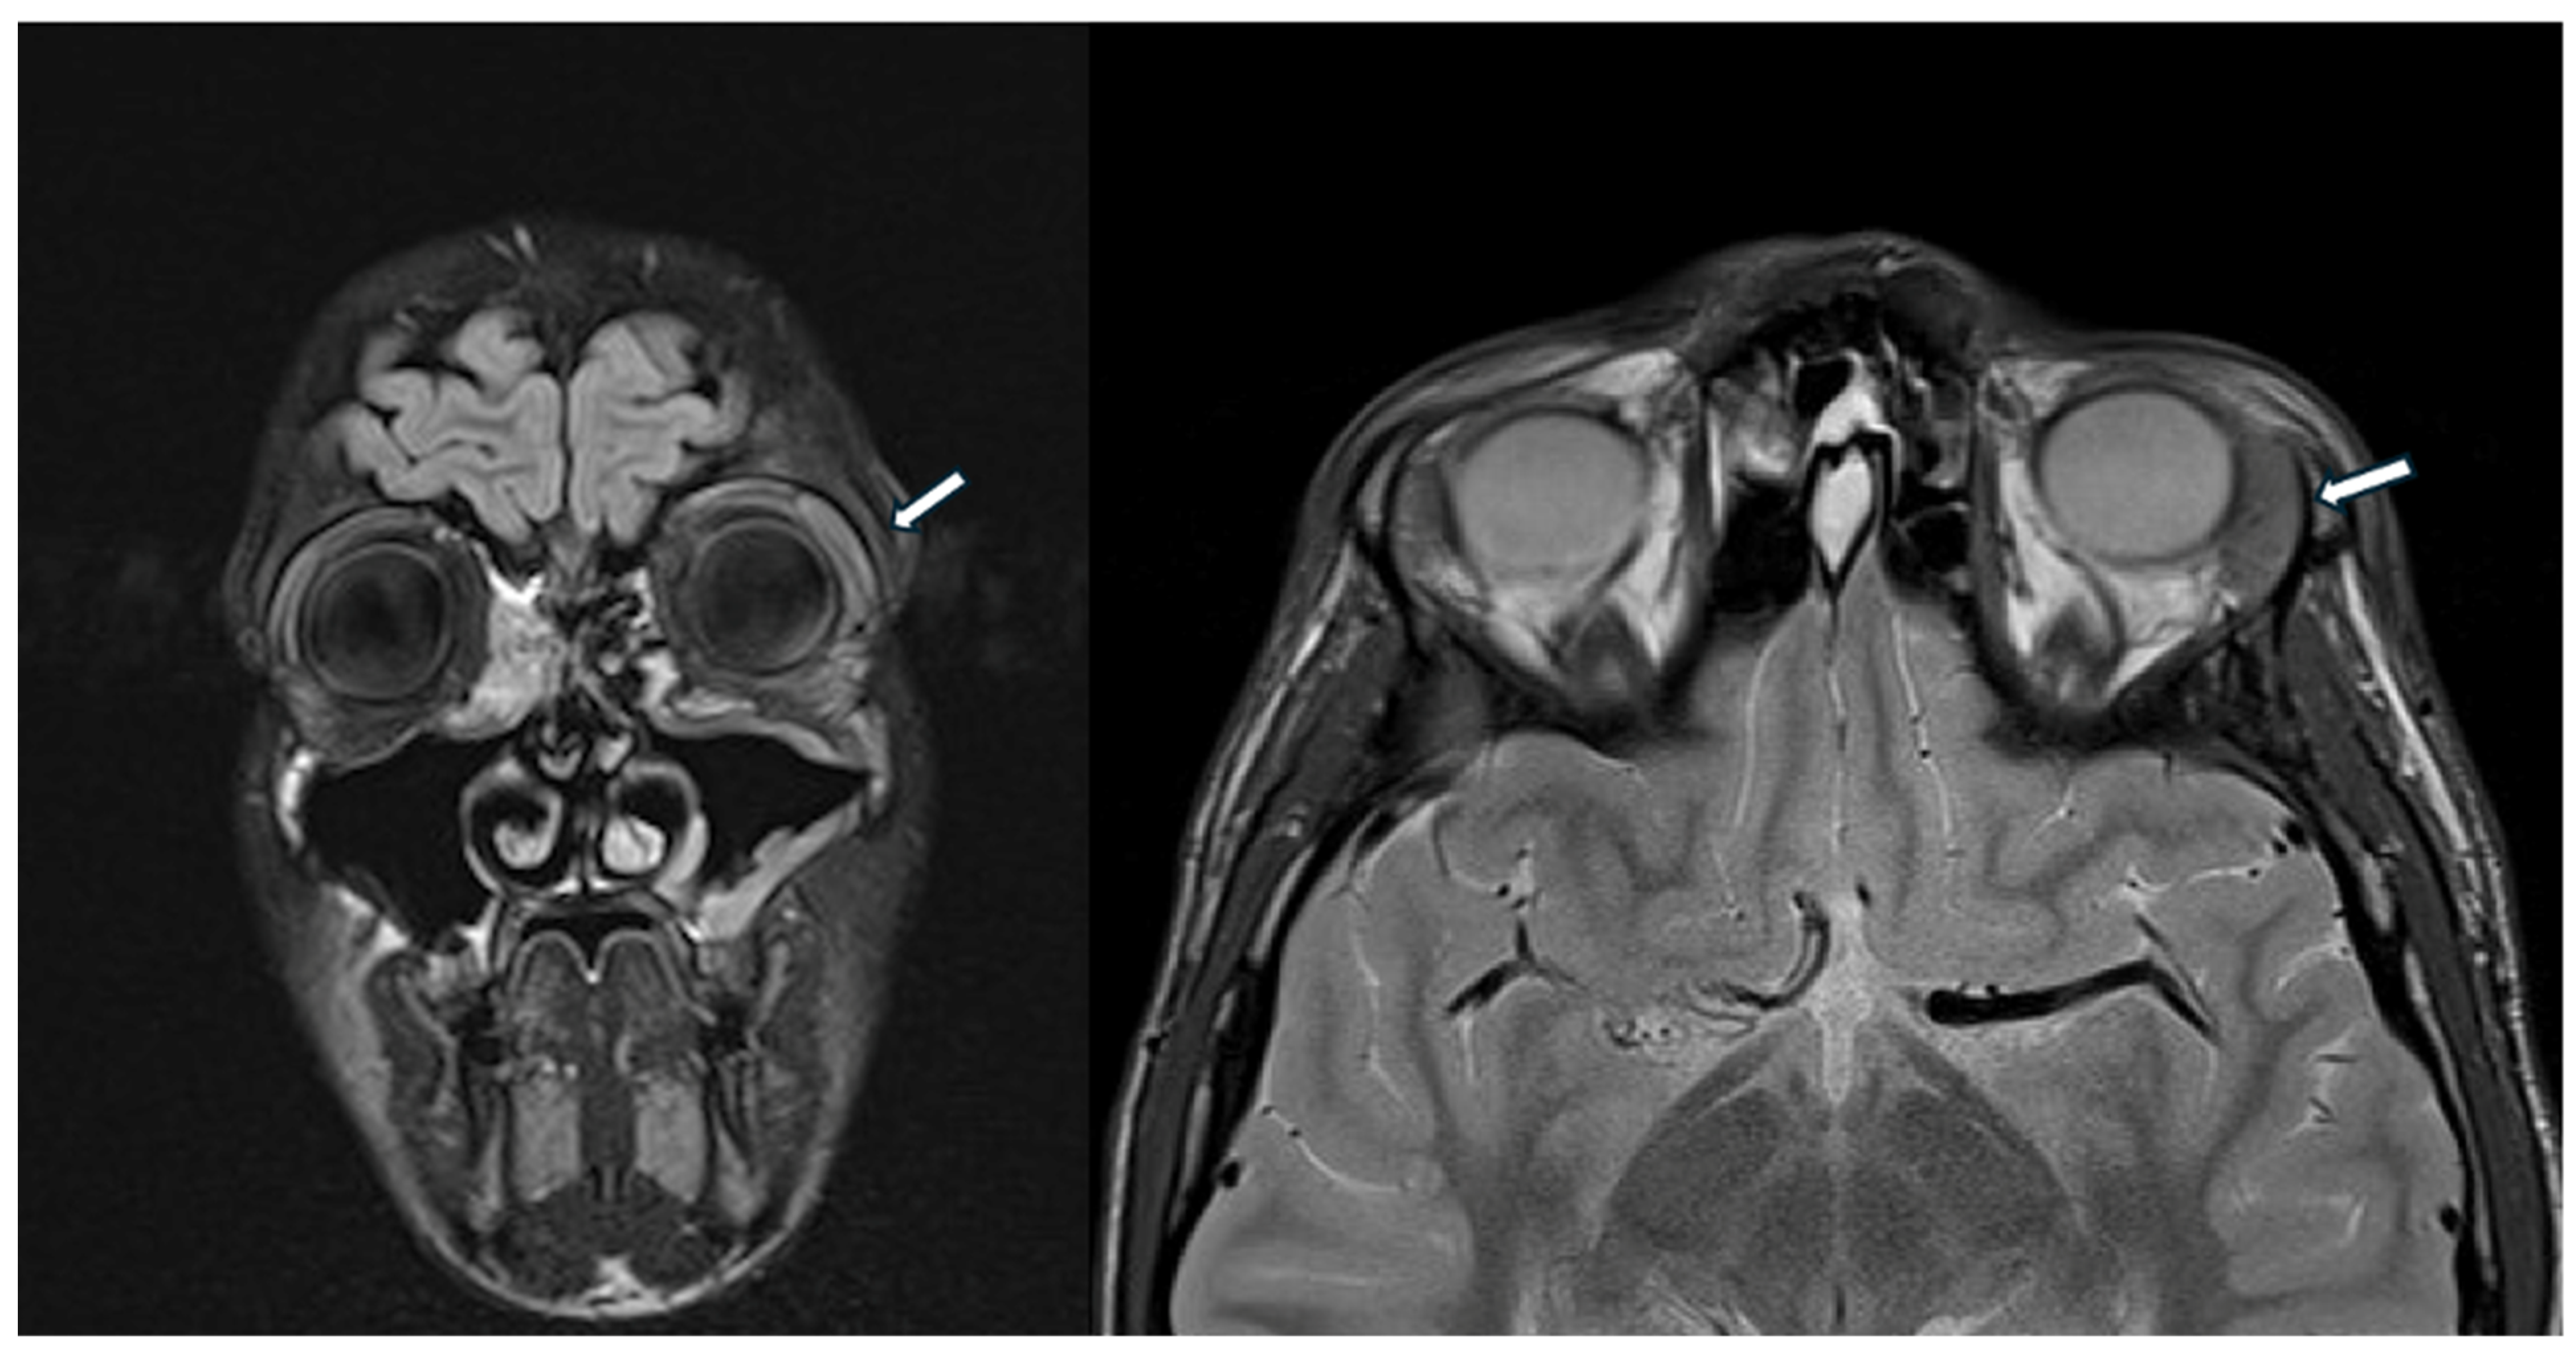

A previously healthy 14-year-old male was referred to our pediatric rheumatology outpatient clinic for recurrent dacryoadenitis. This condition had been diagnosed three years earlier at a local ophthalmological center, where the patient presented with bulbar conjunctival hyperemia and eyeball pain and underwent bulbar ultrasound, optical coherence tomography (OCT), and cranial CT scan, revealing peripalpebral soft tissue swelling on the left portion of the eye. A beneficial treatment with oral and topical antibiotic therapy, along with topical corticosteroids, was initially prescribed. Additionally, corrective lenses have been prescribed for simple hypermetropic astigmatism. However, due to the recurrence of inflammatory episodes coinciding with the tapering of corticosteroids, an orbital MRI was performed, revealing an enlarged left lacrimal gland and minimal peribulbar fluid (Figure 3).

The head MRI shows enlarged left lacrimal gland (white arrow) and minimal peribulbar fluid.

Routine blood exams provided uninformative results, except for increased IgG4 levels (2970 mg/L, nv < 1350 mg/L). Suspecting systemic IgG4-RD, the boy was referred to our pediatric rheumatology clinic.